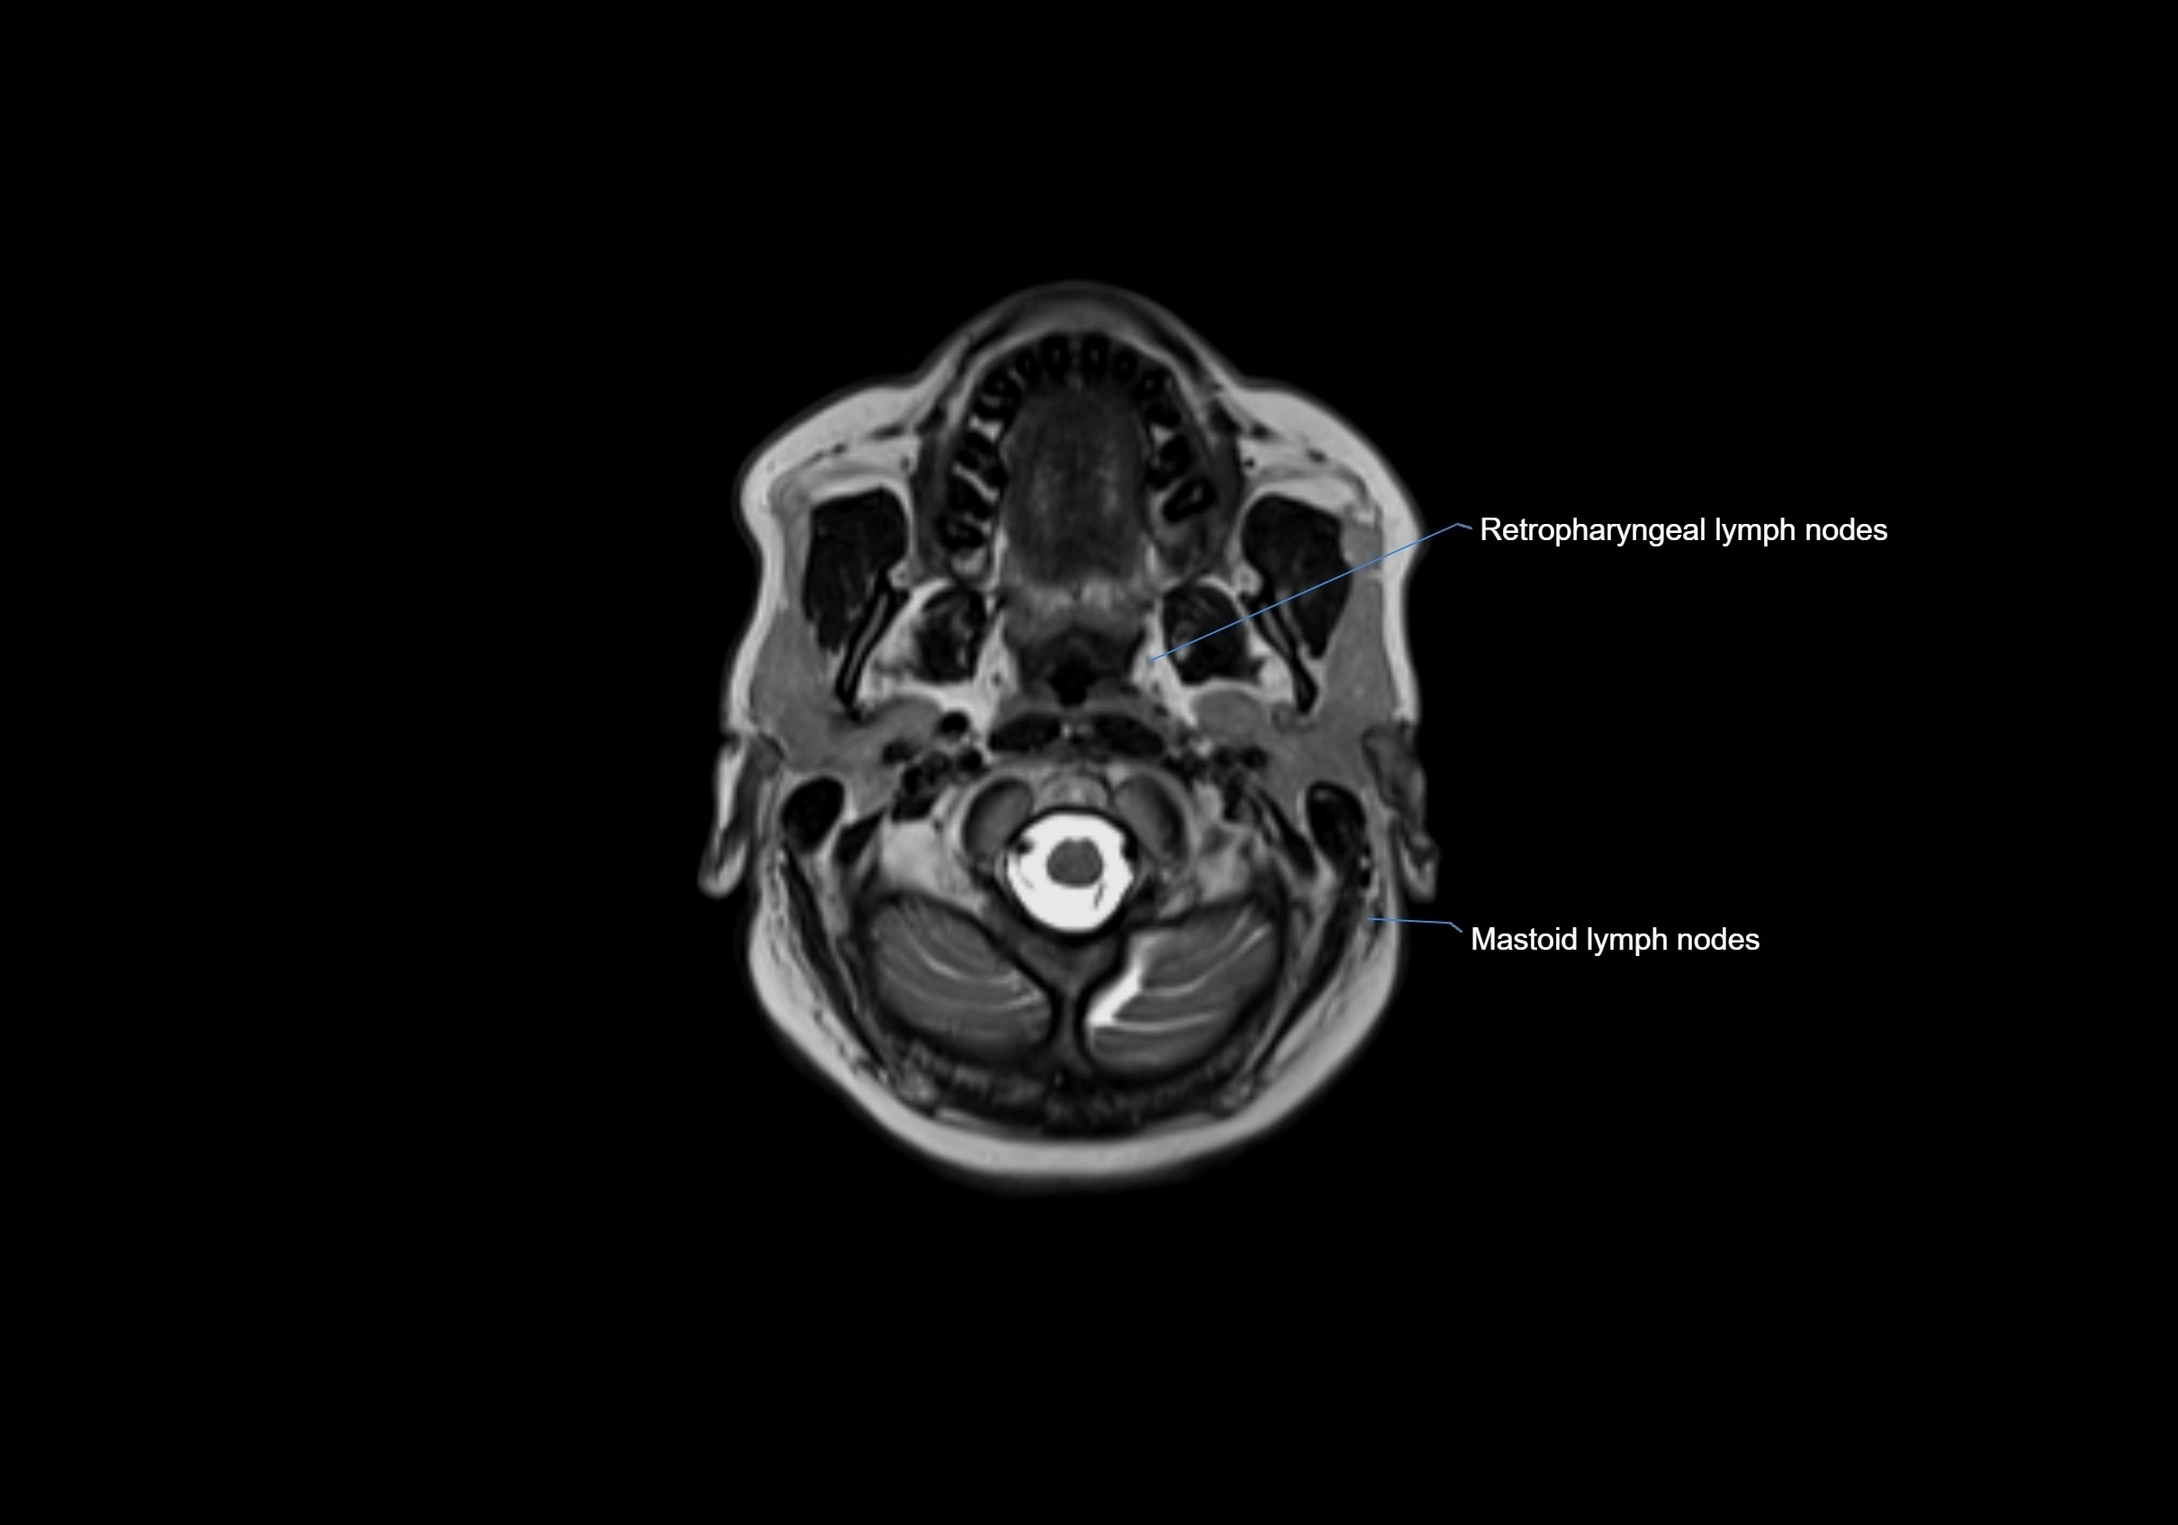

Accessory lymph nodes

Accessory lymph nodes are small, secondary lymph nodes located along the main facial and cervical lymphatic chains, often adjacent to primary lymph nodes, such as preauricular, submandibular, or occipital nodes. They are typically less than 5 mm in diameter, embedded within subcutaneous fat or connective tissue, and may be variable in number and location. These nodes provide additional filtration and immune surveillance for lymph collected from the face, scalp, and neck regions. Accessory lymph nodes are usually non-palpable in healthy individuals but may enlarge in response to infection, inflammation, or metastasis, making them clinically significant.

Location

• Found along primary lymph node chains, including preauricular, submandibular, parotid, and occipital regions

MRI images

image